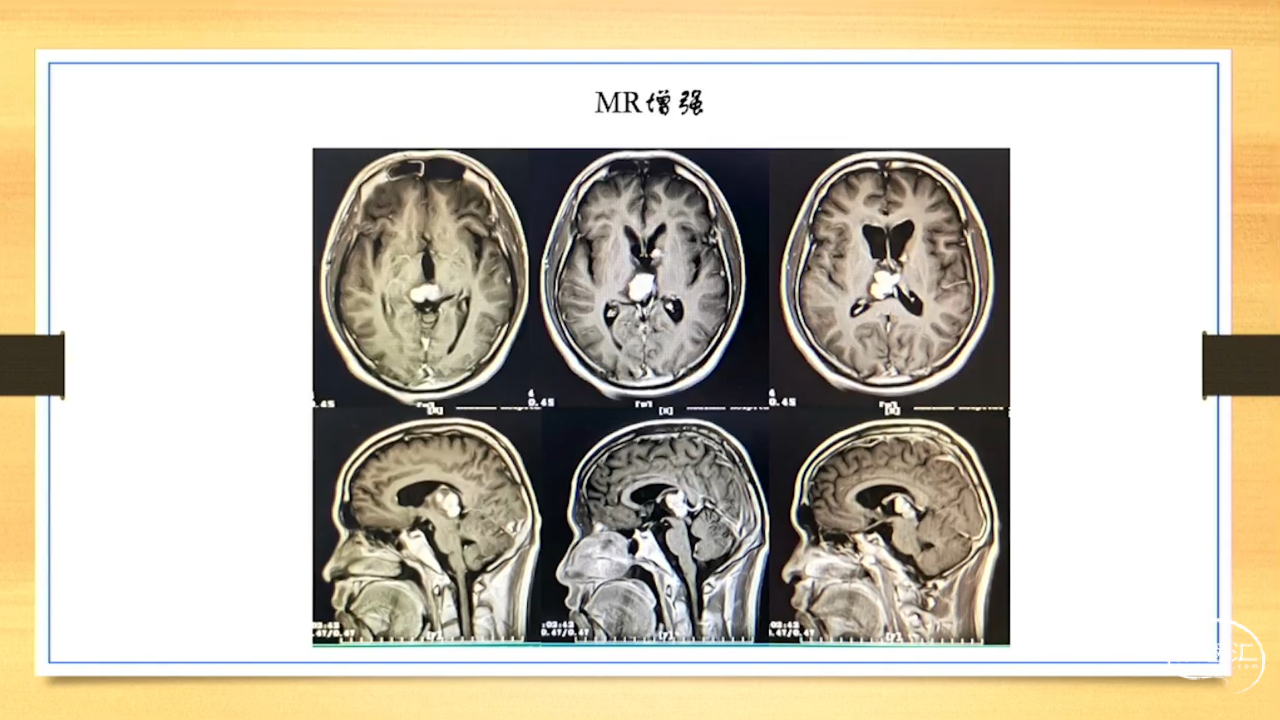

张荣教授:儿童颅内生殖细胞瘤的手术治疗

颅内生殖细胞肿瘤的治疗是手术、放疗、化疗、内分泌及其他多学科的整合治疗。及时、精准、合理的手术治疗是iGCT患者提高生存率、降低并发症、改善神经内分泌功能的关键。